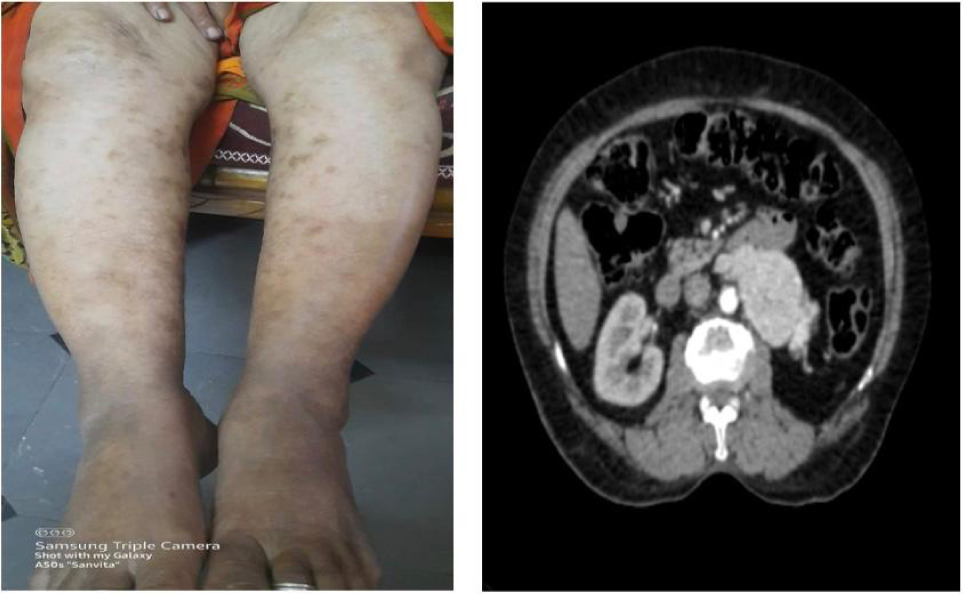

On examination, multiple erythematous, palpable, nonblanching purpuric lesions were observed on both lower limbs (Figure 1). The lesions were of irregular shapes and varied in size. Some of the lesions had vesicles over them. These lesions were most prominent on the ankles and gradually extended up to the knees. The lesions were slightly tender to palpation but no significant warmth or erythema was noted around the lesions. The patient also had a scar over the left lumbar region, which was nontender, consistent with prior nephrectomy. Abdominal examination revealed a nontender, retroperitoneal mass approximately 10 × 8 cm in size in the left lower quadrant. The mass was firm to hard and had an ovoid shape with ill-defined borders. Systemic and pelvic examinations were unremarkable, and there were no signs of lymphadenopathy or organomegaly.

Figure 1: Erythematous palpable nonblanchable purpuric lesions with vesicles.